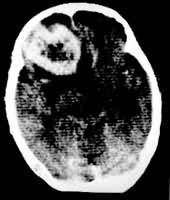

ÄÔÁö£¬70¡«80£¥¿ÉÓÉCT×÷³ö¶¨ÐÔÕï¶Ï¡£¼¸ÖÖ³£¼ûÄÔÁöµÄµäÐÍCT±íÏÖÈçÏÂ:ÐÇÐÎϸ°ûÁöΪÄÔÄÚµÍÃܶÈÖ׿飬¢ñ¡¢¢ò¼¶Õ߽߱çÇå³þ£¬ÎÞÇ¿»¯£¬¢ó¡¢¢ô¼¶Õߣ¬ÂÖÀª²»Õû£¬Óв»¾ùÔÈ»ò»·×´Ç¿»¯£¨Í¼1£©£»ÄÔĤÁö³Ê±ß½çÇå³þ¡¢ÃܶȾùÔȵĸßÃܶÈÖ׿飬ÒÔ¹ã»ùÓë¹ǻòӲĤÏàÁ¬£¬ÓоùÔÈÇ¿»¯£¨Í¼2£©£»´¹ÌåÖ×ÁöΪ°°ÉÏÃܶÈÂԸߵÄÖ׿飬ÓоùÔÈÇ¿»¯£»ÂÑʹÜÁöΪ°°ÉÏ»ìÔÓÃܶȲ¡±ä£¬Óв»¾ùÔÈÇ¿»¯;ÌýÉñ¾ÁöΪÇÅÄÔСÄԽǵͻòµÈÃܶÈÖ׿飬ÓëÔö´óµÄÄÚ¶úµÀÏàÁ¬£¬ÓоùÔÈÇ¿»¯¡£Ð¡ÌýÉñ¾ÁöÓÚÄÔ³ØÔìÓ°CTÉϿɼûСµÄÓëÄÚ¶úµÀÏàÁ¬µÄÖ×¿é£»×ªÒÆÁö³£³ÊƤÖʼ°Æ¤ÖÊÏÂÇø¶à·¢½á½ÚÐÔ²¡±ä£¬ÓÐÃ÷ÏÔµÄÄÔË®Ö×Î§ÈÆ£¬³Ê¾ùÔÈ»ò²»¹æÔò»·×´Ç¿»¯¡£